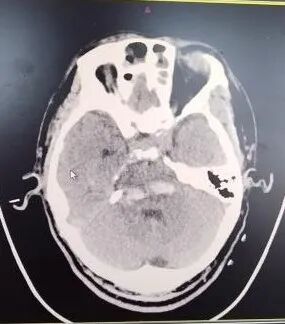

患者李先生于11月5日因“突发昏迷1小时”被紧急送入东海县人民医院急诊抢救室。经头颅CT检查,确诊为凶险的“脑干出血”。入院后,患者病情急速恶化,出血量增多,自主呼吸变得微弱,生命垂危,随即被转入ICU并进行气管插管,依靠呼吸机维持生命。

为确保万无一失,朱龙主任团队术前进行了全面的评估和精密的设计。他们利用先进的三维重建技术,将患者的头颅CT数据转化为立体模型,为李先生“量身定制”了个性化的手术方案和3D打印导航导板。该导板能在术中与患者头部完美贴合,如同为医生配备了“北斗导航系统”,确保穿刺路径精准无误,最大程度避开重要神经和血管,将手术创伤降至最低。